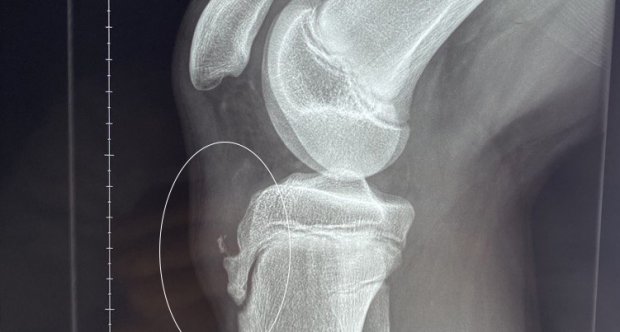

Когда ребенок-спортсмен жалуется на постоянную боль под коленом, и при этом он активно растет, то это может быть болезнь Шляттера. Обычно ее страдают подростки, особенно мальчики 10-16 лет, которые совмещают интенсивные тренировки, прыжки, бег или футбол с быстрым ростом костей. В результате месте воспаления появляется боль, припухлость и дискомфорт.

При быстром росте костей подростка точка крепления сухожилия мышцы бедра к большеберцовой кости оказывается под повышенной нагрузкой. Если в этот период ребенок активно занимается спортом?(баскетболом, футболом, гимнастикой, скачками), то?эта нагрузка становится хронической.

Сенсорная чувствительность может быть еще нормальной, но участок крепления сухожилия уже «раскаляется» от повторяющихся нагрузок, появляется боль при приседании, прыжках, спуске, подъеме по лестнице. Со временем без лечения возможны осложнения: хроническая боль, псевдоартроз, ранний артрит колена.